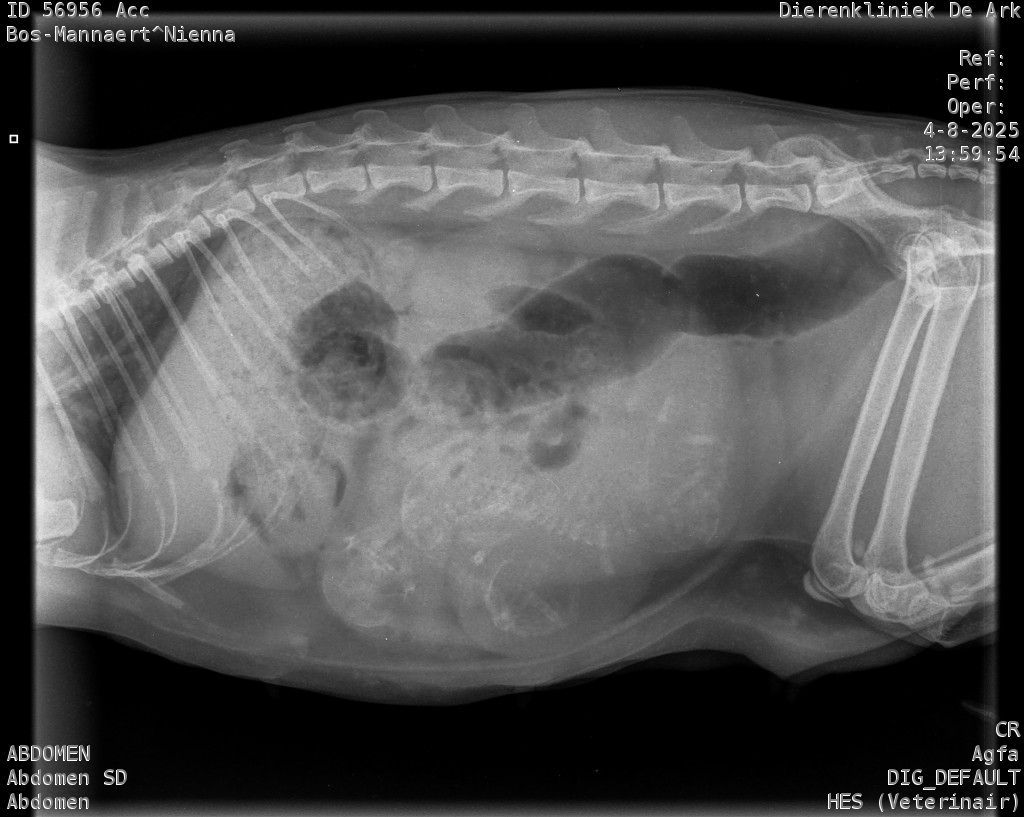

Zondag zag het er naar uit dat Nienna haar melkproductie een beetje op gang kwam. Maandag hebben we dan ook gelijk een checkup gepland en is er een foto gemaakt.

Er waren duidelijk 3 kittens zichtbaar. Dus kreeg ze gelijk een rustig plekje in de woonkamer. Maandag avond was het al aan het rommelen, uiteindelijk zette de bevalling pas goed door in de nacht van dinsdag op woensdag 6 augustus.

Op de foto was te zien dat de 3 kittens waarschijnlijk allemaal in de stuit lagen. Gezien ik niet wist hoe ver ze al was in de dracht en of de kittens groot zouden zijn konden we niet meer dan afwachten.